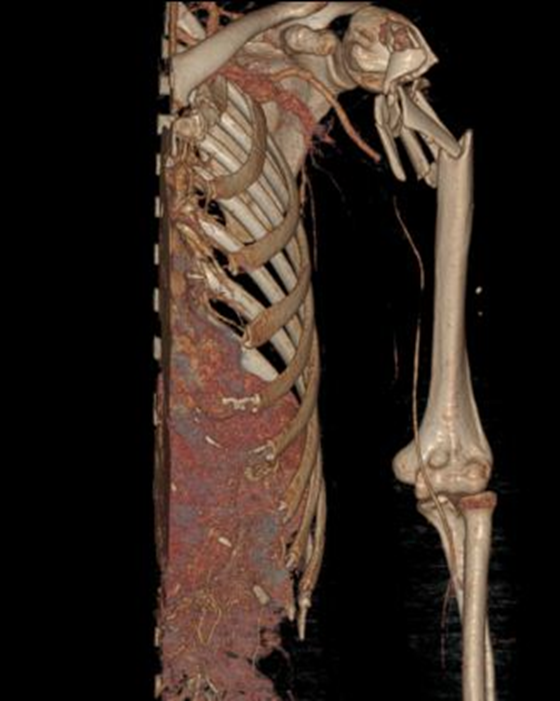

一名60岁女性患者因外伤导致左上臂疼痛出血,被诊断为“左肱骨开放性骨折”紧急送至湘雅常德医院骨科。接诊医生发现患者左侧上肢血运障碍,可能存在高位肱动脉或腋动脉损伤风险。为挽救肢体,骨科创伤组迅速评估患者情况:其肱骨外科颈粉碎性骨折,肱骨头翻转游离,血管CTA提示腋动脉与肱动脉移行区损伤可能。杨雷主治医师制定了急诊清创+血管探查修补+外固定架固定术的初步方案,并计划二期进行肱骨近端骨折切开复位、取腓骨植骨及内固定术。

术前:外科颈内侧骨片尖端向内侧突进